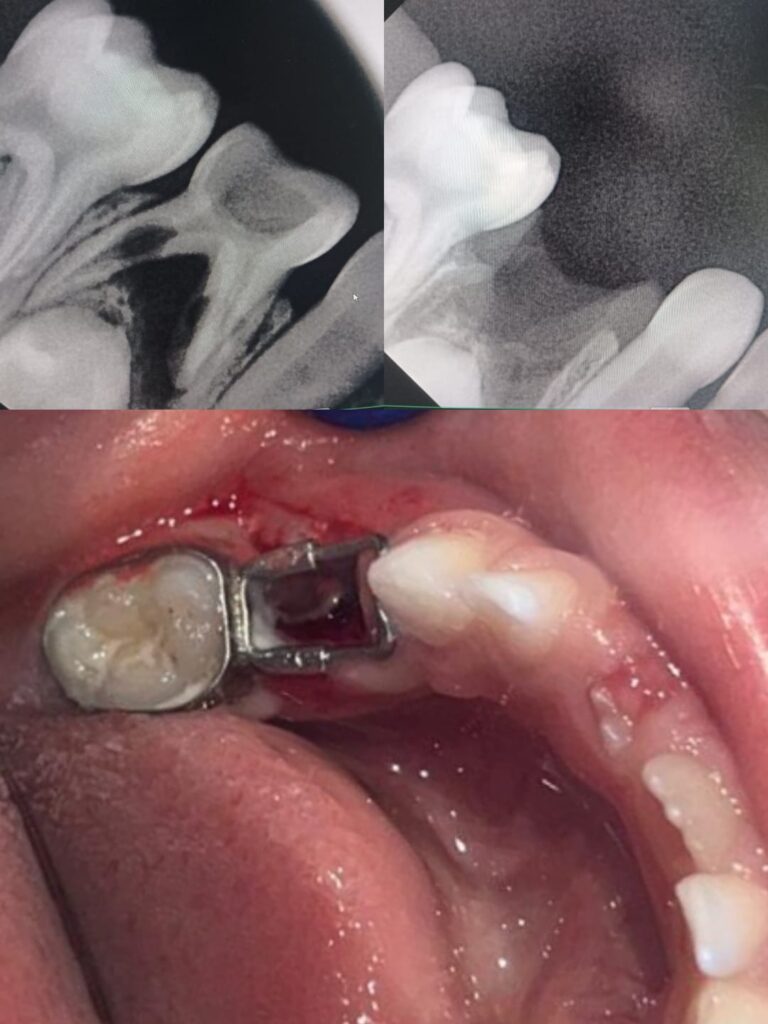

1. Fixed Space Maintainer

This type is cemented to adjacent teeth and cannot be removed by the child.

Common types include:

These are most commonly used in pediatric dentistry.